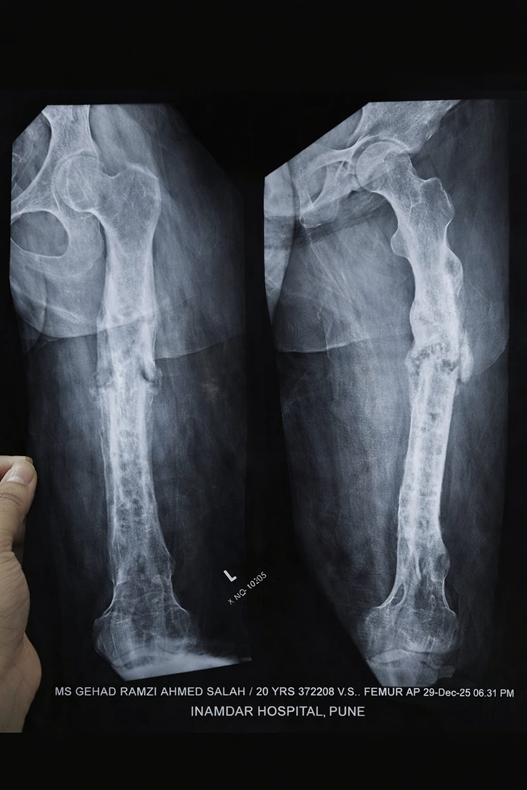

In this case-based educational blog, we discuss the condition, radiological findings, and the advanced orthotic solution provided to a 21-year-old female patient with femoral shaft non-union and callus formation.

In this 21-year-old patient, the X-ray findings showed:

- Persistent fracture line at midshaft

- Significant callus formation

- Cortical irregularity

- No complete bridging union

The presence of callus indicates that the body is attempting to heal — a positive sign. This type of pattern is often described as hypertrophic non-union, meaning biology is good but stability is insufficient.